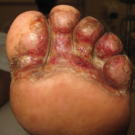

Dustin Marks; Kristina Paley, MD

A 57-year-old white male with a history of diabetes and hypertension presents with a 3-month ulcer on his left, plantar foot.